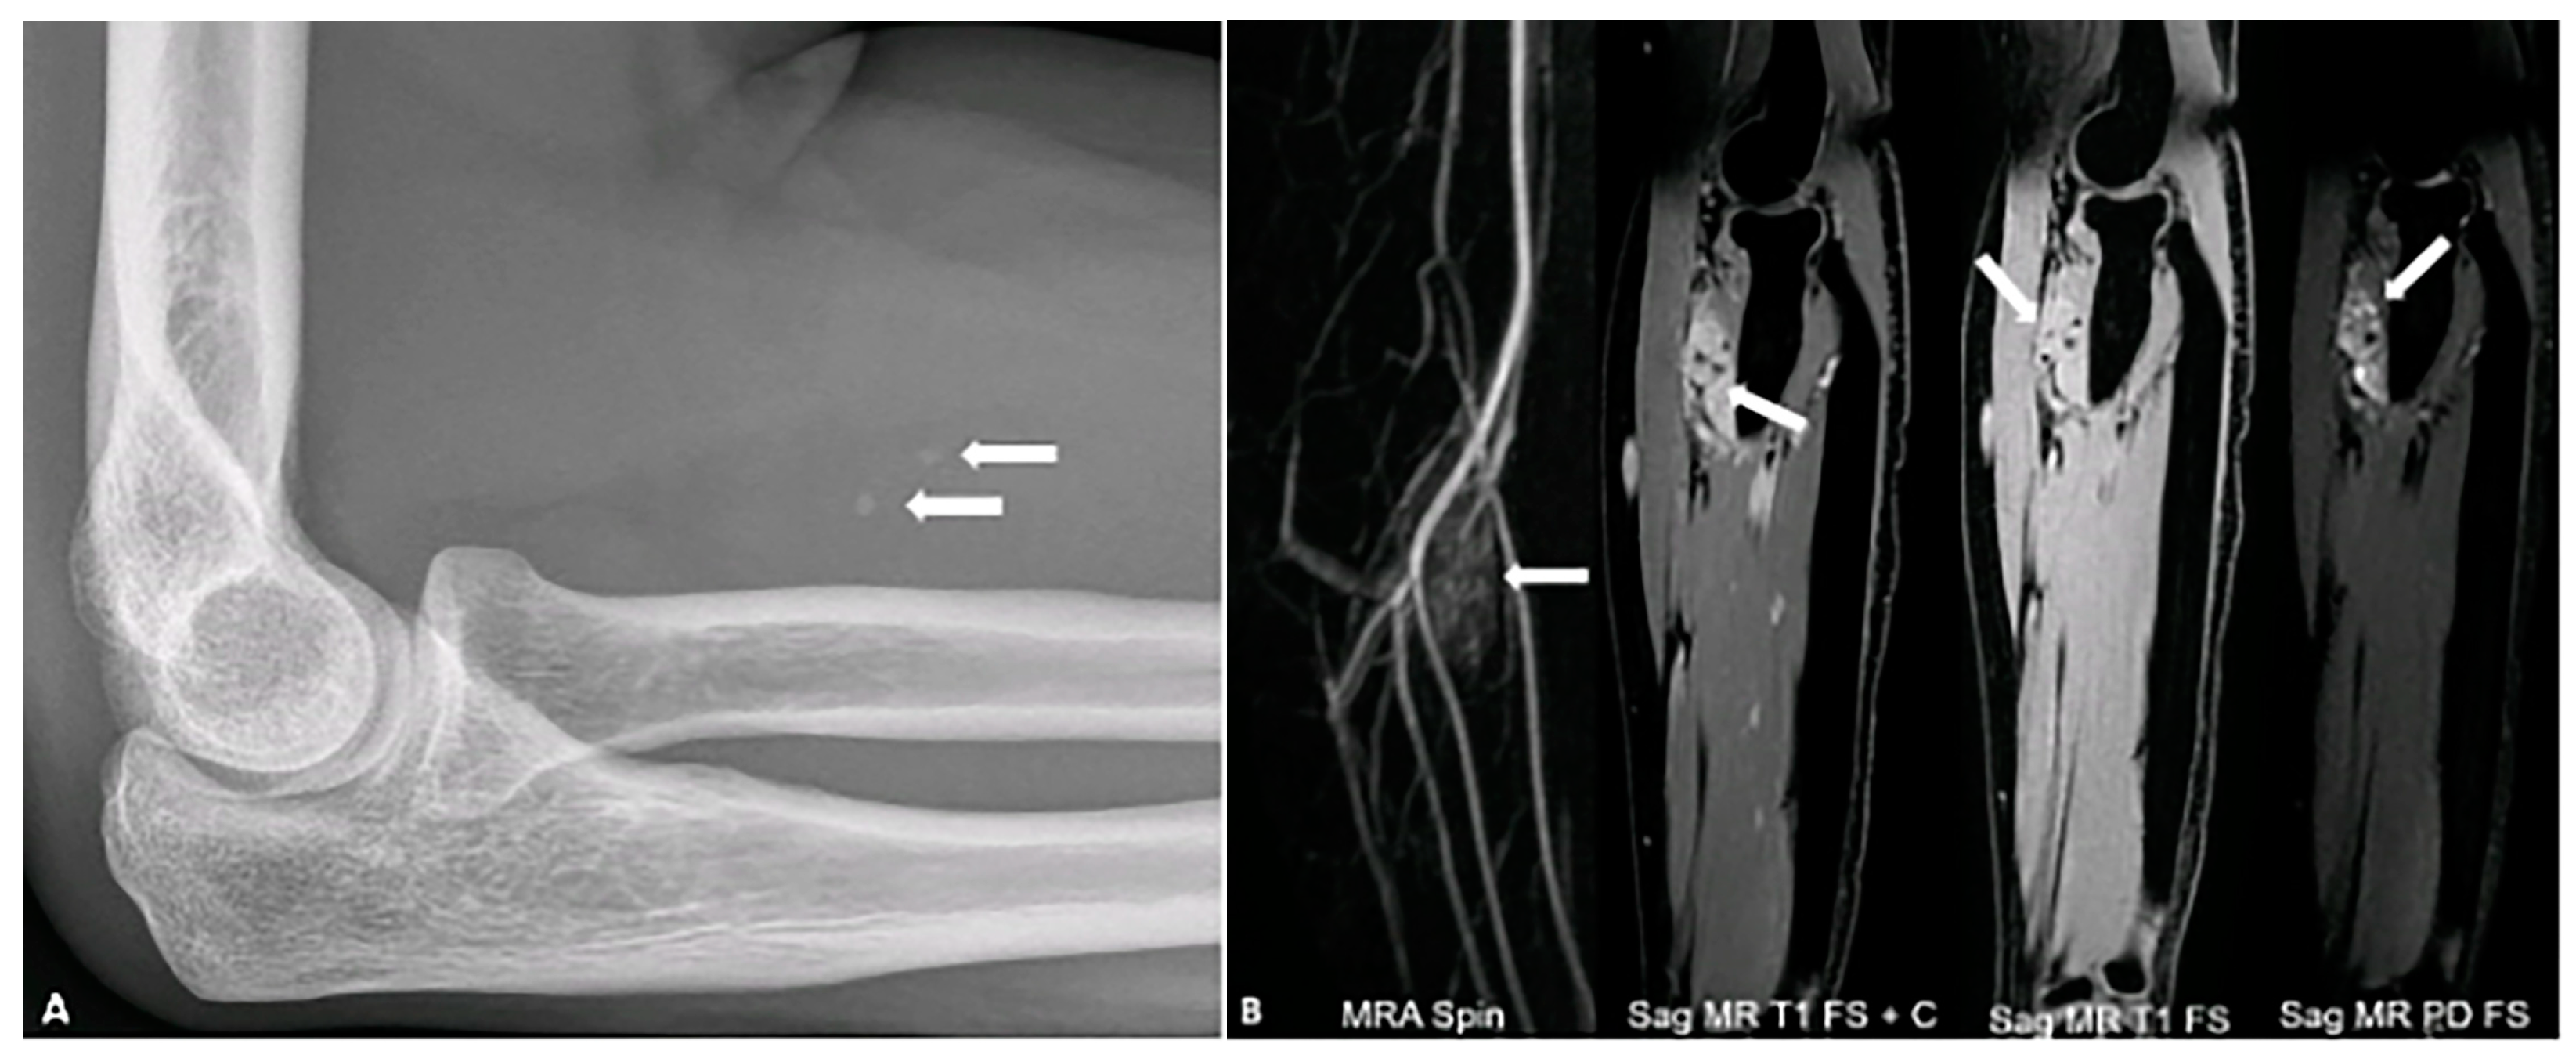

4.3. Calcifying Aponeurotic Fibroma

- Pena-Burgos, E.; Iglesias-Urraca, C.; González-García, M.; Rodríguez-García, A.; Tapia-Viñe, M.; Ortiz-Cruz, E.; Pozo-Kreilinger, J. Calcifying aponeurotic fibroma: Radiologic-pathologic analysis of ten cases and review of the literature. Ann. Diagn. Pathol. 2022, 61, 152056. [Google Scholar] [CrossRef]

- Sekiguchi, T.; Nakagawa, M.; Miwa, S.; Shiba, A.; Ozawa, Y.; Shimohira, M.; Sakurai, K.; Shibamoto, Y. Calcifying aponeurotic fibroma in a girl: MRI findings and their chronological changes. Radiol. Case Rep. 2017, 12, 620–623. [Google Scholar] [CrossRef]

- Kang, J.H.; Lee, K.; Yoo, H.J.; Chae, H.D.; Hong, S.H.; Choi, J.Y. Ultrasound and magnetic resonance imaging features of calcifying aponeurotic fibromas. J. Ultrasound Med. 2020, 39, 1299–1306. [Google Scholar] [PubMed]